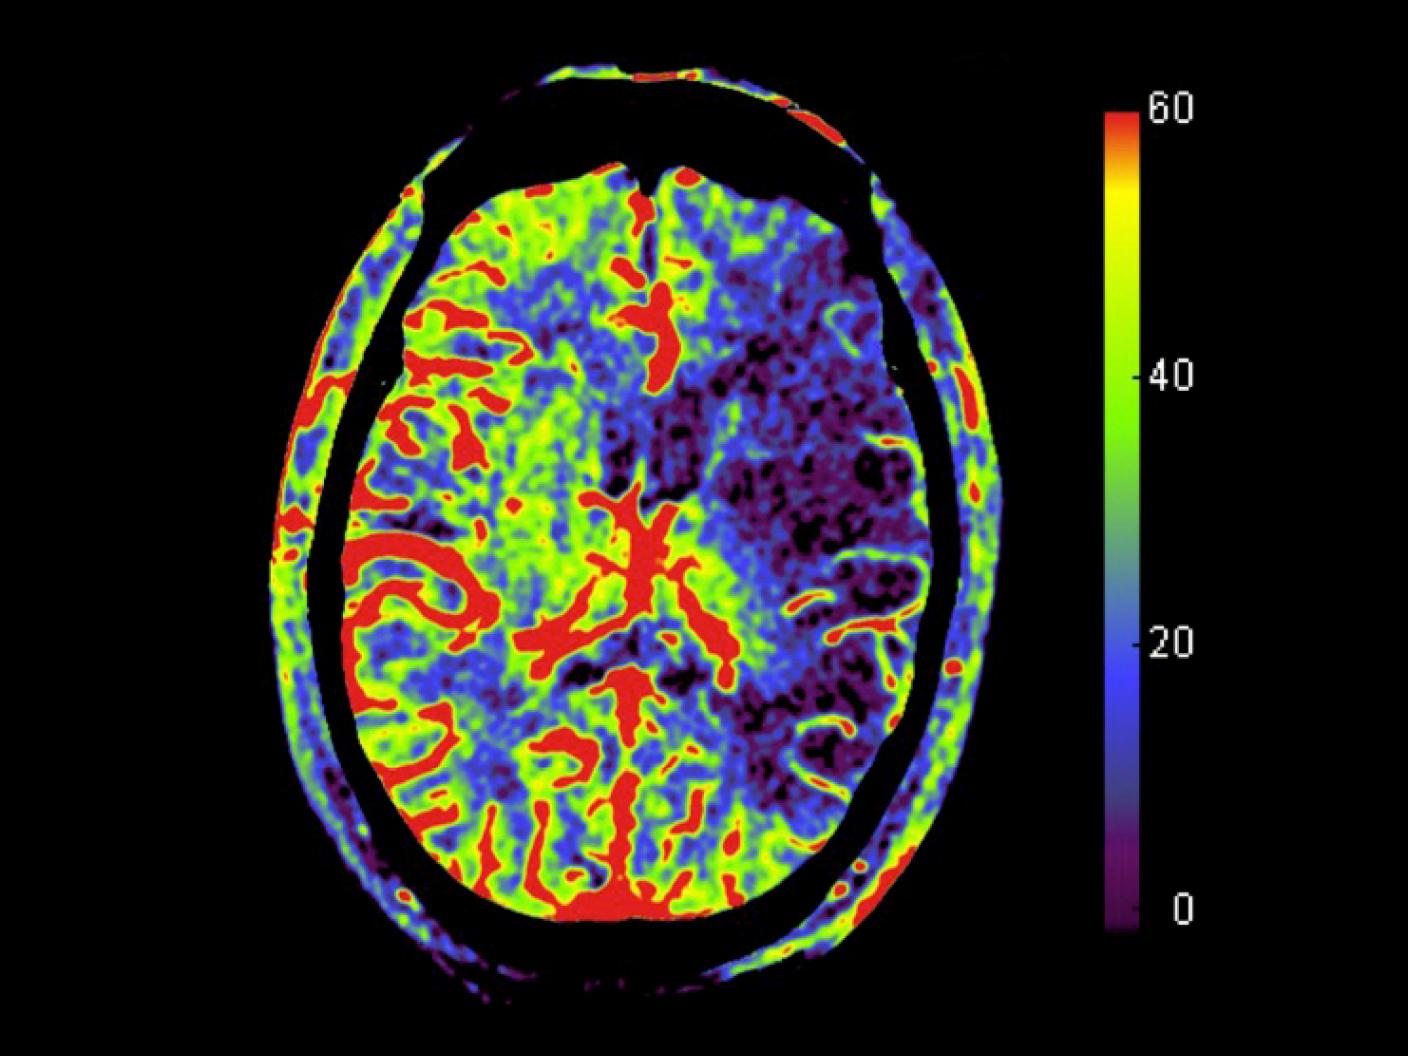

Pre-treatment: A parenchymal cerebral blood volume (syngo Neuro PBV Neuro) map depicted a large area of hypoperfusion in the corresponding left MCA territory.

Courtesy: Prof. Wan-You Guo, MD, Taipei Veterans General Hospital, Taiwan

Post-treatment: A syngo Neuro PBV Neuro map depicted the recovery of CBV values (circle) in part of the hypoperfused parenchyma after revascularization.

syngo DynaPBV Neuro depicted a large area of hypoperfusion in the corresponding left MCA.